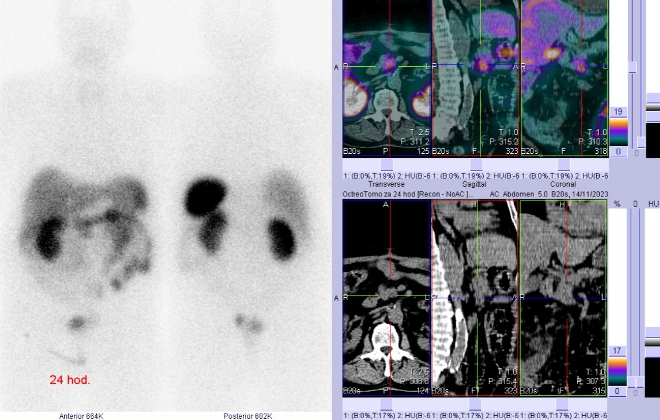

(přípravek OctreoScan firmy Curium Netherlands B. V.) a provedli pomocí hybridní tomografické scintilační kamery Symbia T2 firmy Siemens opatřené kolimátory pro střední energie planární celotělovou scintigrafii a cílenou tomografickou scintigrafii (SPECT) břicha a pánve kombinovanou s CT za 4 a 24 hod.

/ Obr. č. 2: Celotělová scintigrafie a SPECT/CT za 4 hod. po aplikaci OctreoScanu.

Popis: Za 4 a 24 hod. je patologické ložisko zvýšené depozice radioindikátoru v uzlině u hlavy pankreatu. Jinak pozorujeme fyziologickou depozici radioindikátoru ve slezině, játrech, ledvinách, močovém měchýři, střevech.

Závěr: patologické ložisko se zvýšenou hustotou somatostatinových receptorů v uzlině u hlavy pankreatu. Nález svědčí pro uzlinovou metastázu neuroendokrinního nádoru.

U hlavy pankreatu jsme prokázali uzlinovou metastázu neuroendokrinního tumoru tenkého střeva.